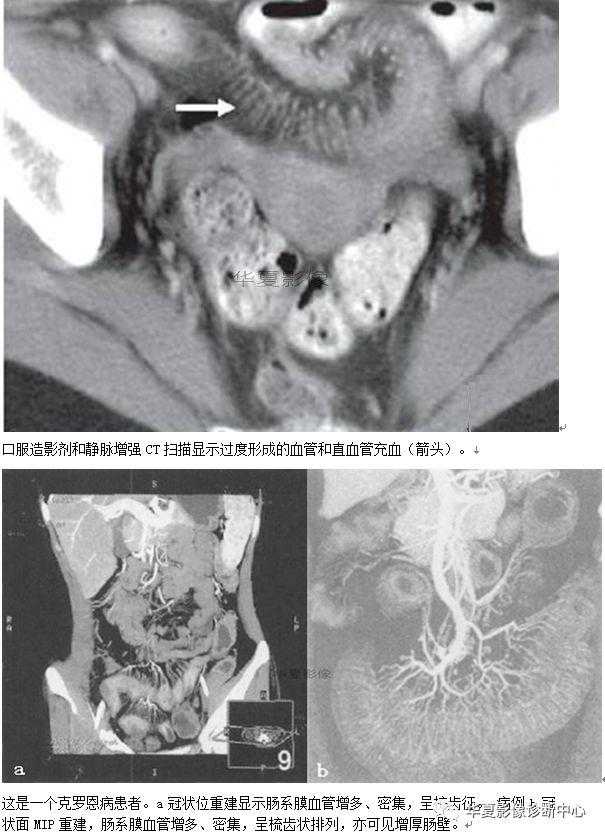

037:梳齿征

腹盆腔C扫描时,于回肠的系膜侧可见多个直管状,扭曲的阴影排列成梳齿状。供应小肠的动脉由肠系膜上下动脉发出,于肠系膜内形成一系列相互吻合呈弓状的小肠动脉支。其终末分支(直小动脉)在空肠比较长且相巨间距离较大,而在回肠则比较短相对距离较近。

因此,当回肠系膜内的直小动脉增多、扭曲、扩张,相互间距离增大时,在CT增强扫描时表现为梳齿状,称为梳齿征。这是由于发生炎症性肠病时,受累肠管的血流增多,相应的肠系膜呈纤维脂肪增殖所致,多见克罗恩病。克罗恩病是累及肠壁全层的慢性内芽肿性炎症性疾患,消化道全程均可发病,但以末端回肠及近端结肠最为多见。

最早期的镜下发现为扩大的淋巴滤泡以及鹅口癌样小溃疡,溃疡常常在双对比钡剂造影时能够见到,而CT扫描由于空间分辨率较低的原因常常难以分辨。克罗恩病最常见的CT表现为肠壁增厚,有超过82%的病人可以见到,通常增厚达5~10mm,甚至20mm。增厚的肠壁多见于末端同肠,也可见于消化道的其他部分。

在急性期,受累的肠壁呈分层表现,CT上呈靶样或双晕状表现,这可能是由于黏膜下水肿或肠壁脂肪浸润所致.肠壁增厚并不是克罗恩病特有的表现,事实上,非活动性溃疡性结肠炎的患者占60%以上,而仅有8%患者有克罗恩病。

此外也可见于放射性肠病、移植物抗宿主病及肠比慢性缺血。发炎的黏膜和浆膜层可在CT增强扫描时强化.强化程度和疾病的临床活动性有关。病程较长的患者,肠壁纤维化,分层现象消失,CT扫描时受累肠壁密度均匀。在克隆氏病中肠系膜经常受累。克罗恩病常常累及肠系膜而致纤维脂肪样增殖,也称为肠系膜脂肪蔓延,这是导致小肠检查中出现肠襻分离的主要原因。小场和肠系膜之间的脂肪界面消失,由于发生炎症改变使脂肪密度升高20~60Hu。肠系膜的纤维脂肪浸润仅是形成梳齿征的部分原因,此外更主要的原因是血管从所在肠管的浆膜面分离,在CT扫描时血管直立突出并彼此分离而形成梳齿状。

同时在CT上还可以见到淋巴结肿大,通常大小为3~8mm,如果淋巴结肿大10mm,则要排除发生淋巴瘤(或癌),因为这两种病在克罗恩病患者中的发生率要高于普通人群。

在已知患有克罗恩病的患者中,如果出现了上述的由肠系膜血管增生,扭曲、扩张,以及因直小血管的突出而形成的梳齿征时,表明疾病有急性恶化的趋势,有文献报道克罗恩病患者肠周血管显著提示疾病活动、进展或广泛蔓延。第一次出现临床症状的患者进行CT检查发现上述表现时,可以提出克罗恩病诊断的可能性,但并不是绝对特异性的征象,因为在狼疮性肠系膜血管炎中也可以出现类似的梳齿征。

有文献报道系统性红斑狼疮出现急性腹痛时,在CT检查发现缺血性肠病的患者中梳齿征的出现率为87%。还有一些其他的疾病在发展过程中可以出现血管扩张,比如血管病(包括结节性多动脉炎,Henoch-Schonlein综合征、显微镜下多血管病,贝赫切特综合征等)、肠系膜血栓拴塞、绞窄性肠梗阻,溃疡性结肠炎等。临床病史、疾病的分布以及其他相关检查对疾病的鉴别诊断有一定帮助。梳齿征的出现对于鉴别淋巴瘤以及转移瘤有较大帮助,因为这两种病通常为少血供的。